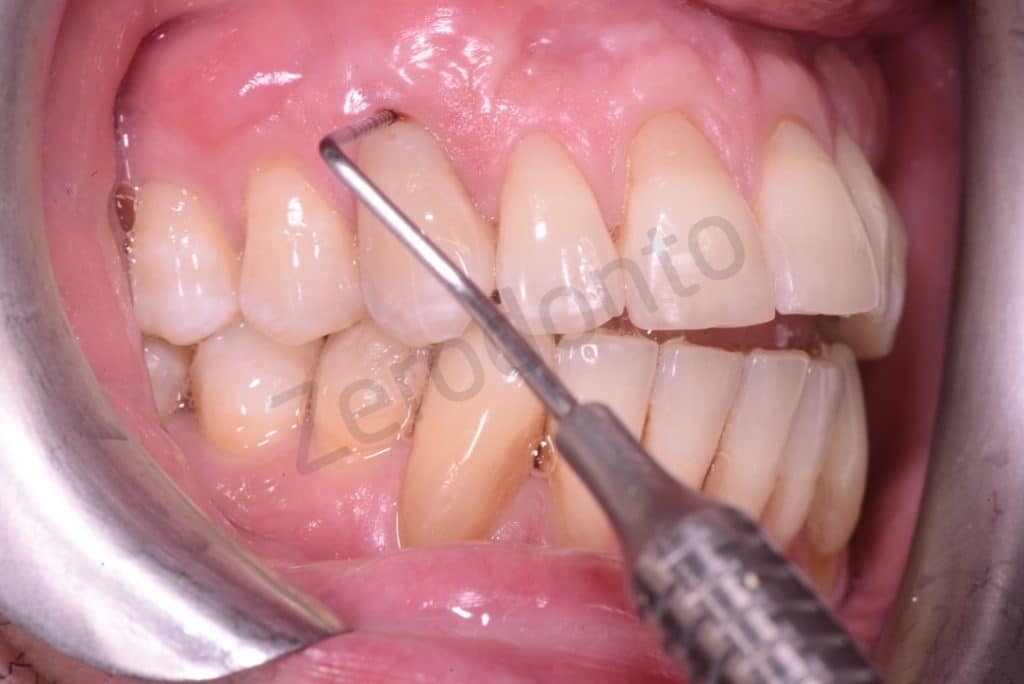

Probing resorption

4mm lesion

A coronal repositioning flap first at partial thickness then total thickness and finally a periosteal incision to mobilize the flap were performed. The anatomical papillae were disepithelized to allow the sliding of the surgical papillae.